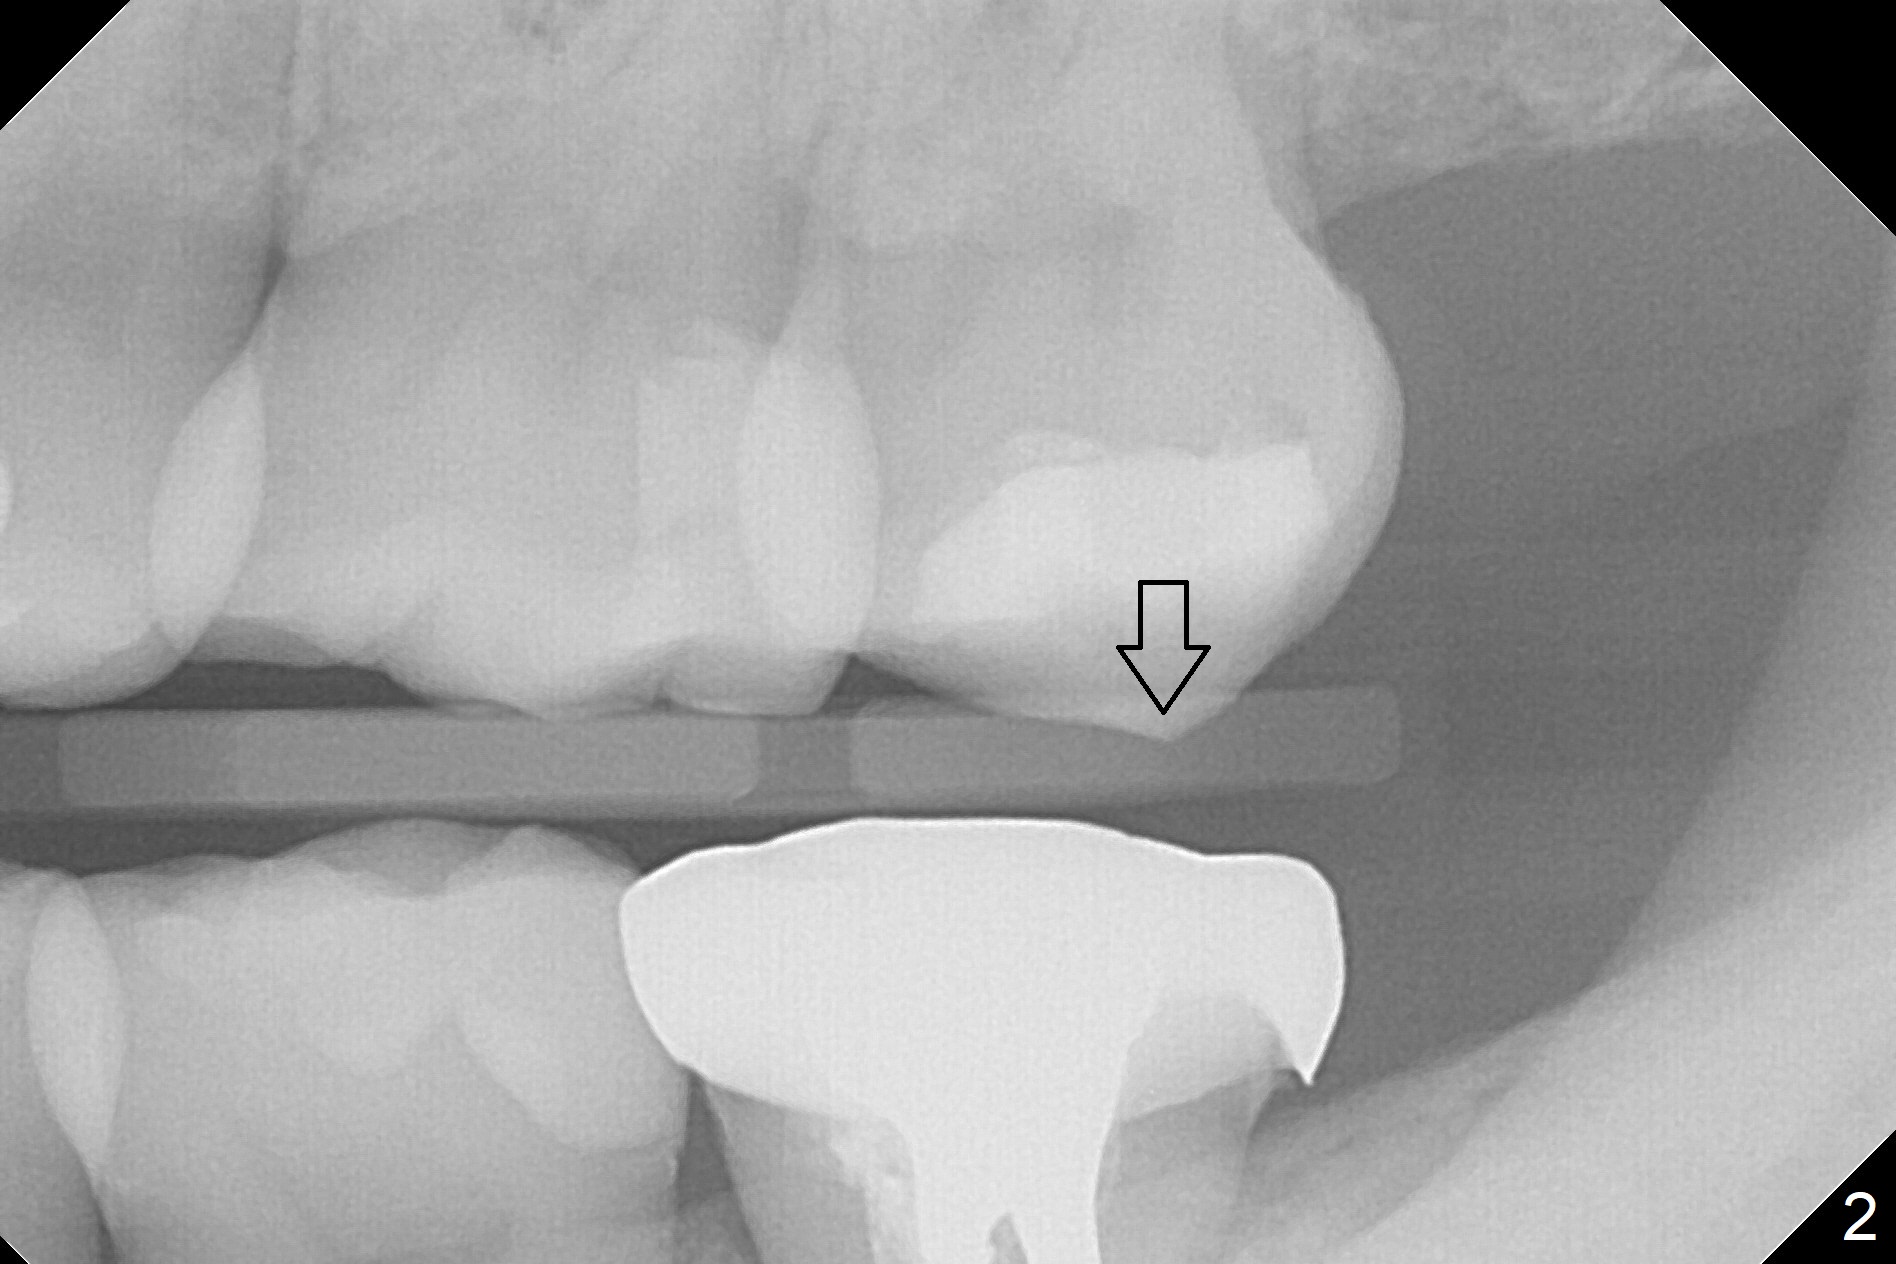

A 34-year-old woman has been our patient for >5 years. Since then, the teeth #17 and 32 have been extracted (Fig.1 x). The main issue is the metal crown at #18, which had occlusal perforation. The crown was recemented once. The mesiolingual margin is wide and subgingival. After redo, the Zirconia crown fractured once and finally dislodged (Fig.3), partially due to #15 supraeruption (Fig.2 arrow, trimmed during crown redo). Following extraction, use starter drill and 2 mm drill with 8 mm stopper to initiate osteotomy in the mesial slope of the socket (Fig.3 yellow line). The stopper should stop prematurely in the mesiocoronal aspect of the mesial slope, the depth should be a little longer than 5.6 mm (Fig.3 pink line). Insert a marked parallel pin for X-ray depth confirmation. Considering the opposing tooth supraeruption, a probably 5x10 mm SM implant will be placed deep with a cemented abutment with 1 mm cuff. But at first a temporary abutment will be used most likely. Make a provisional as wide as possible apically so that it is easy to take impression later on.